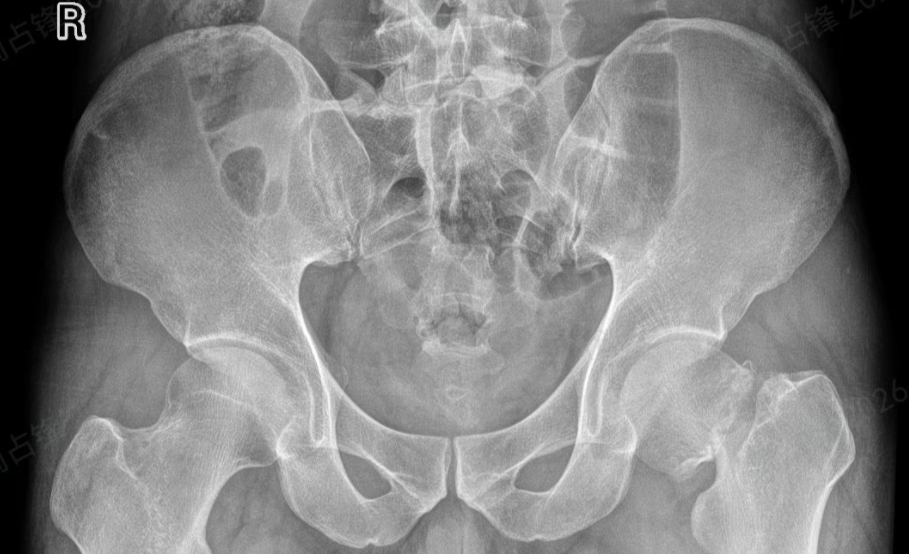

大年三十,王先生在浙江意外摔倒,左侧髋部剧痛难忍,被紧急送往当地医院,确诊为左侧股骨颈骨折。

接诊的骨科团队第一时间为他完善了影像学检查,明确了骨折分型和手术指征。